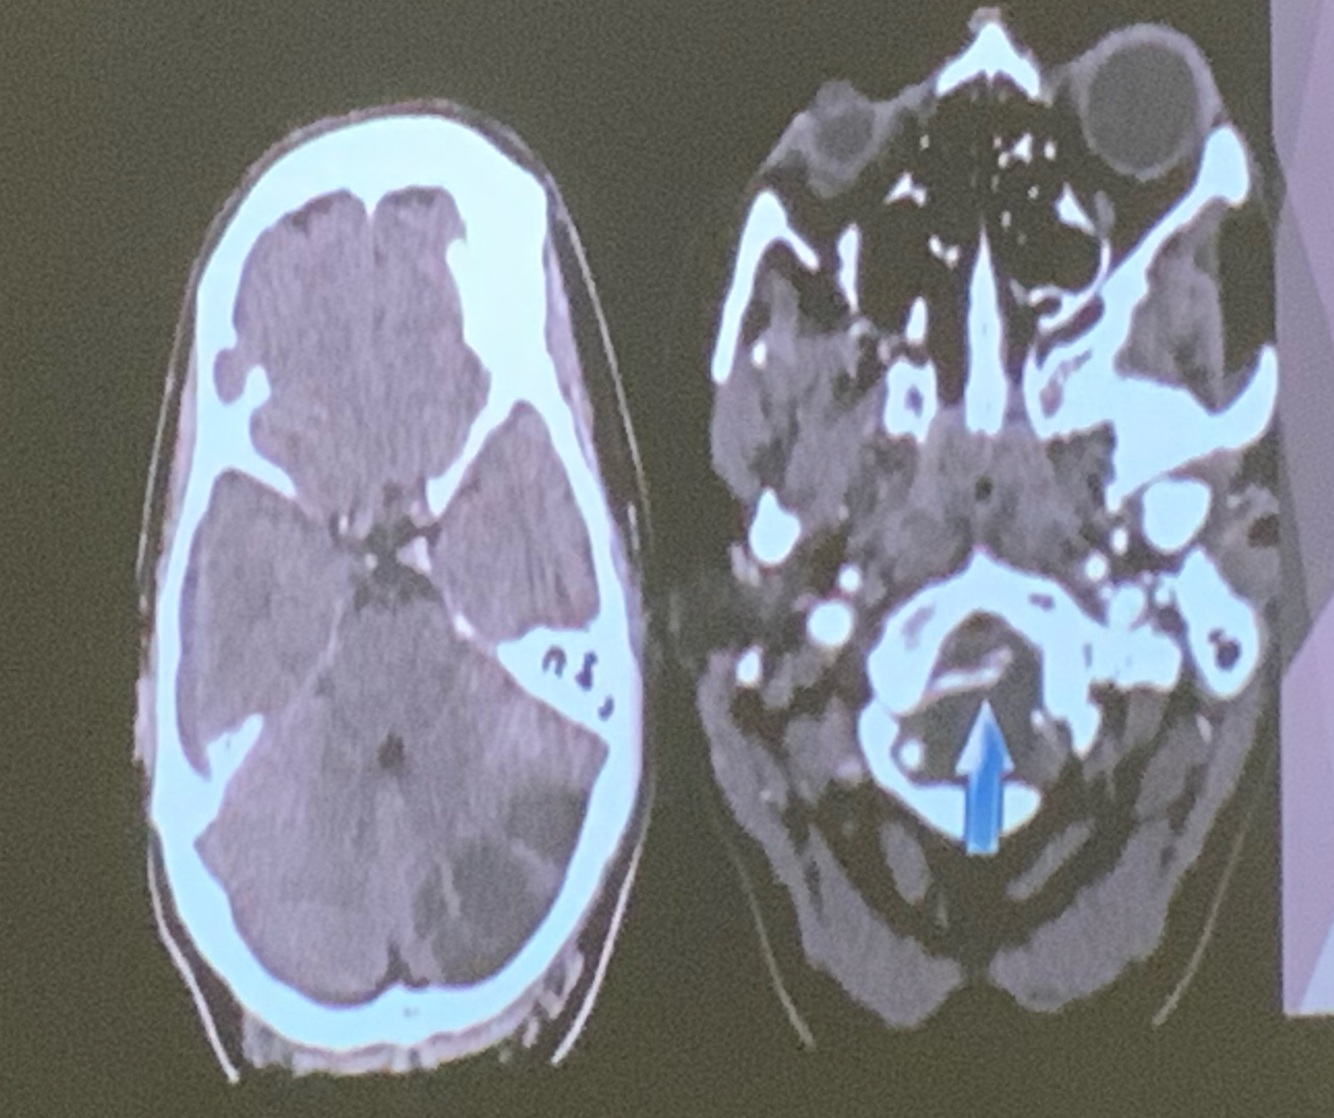

Que arteria se encuentra afectada

A

PICA

Q